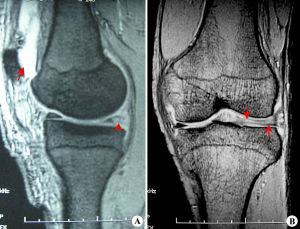

膝關節半月板影像片針灸拔罐、針灸、按摩等理療方式可以改善局部血液循環、起到活血化瘀、舒筋通絡的作用,對於心腦血管疾病的後遺症、風濕類風濕後期康復效果顯著。但只是輔助治療;半月板損傷與一般的關節痹症不太相同,它主要是關節發生無菌性炎症,簡單的活血化瘀、舒筋通絡根本無法從根本上祛除無菌性炎症。